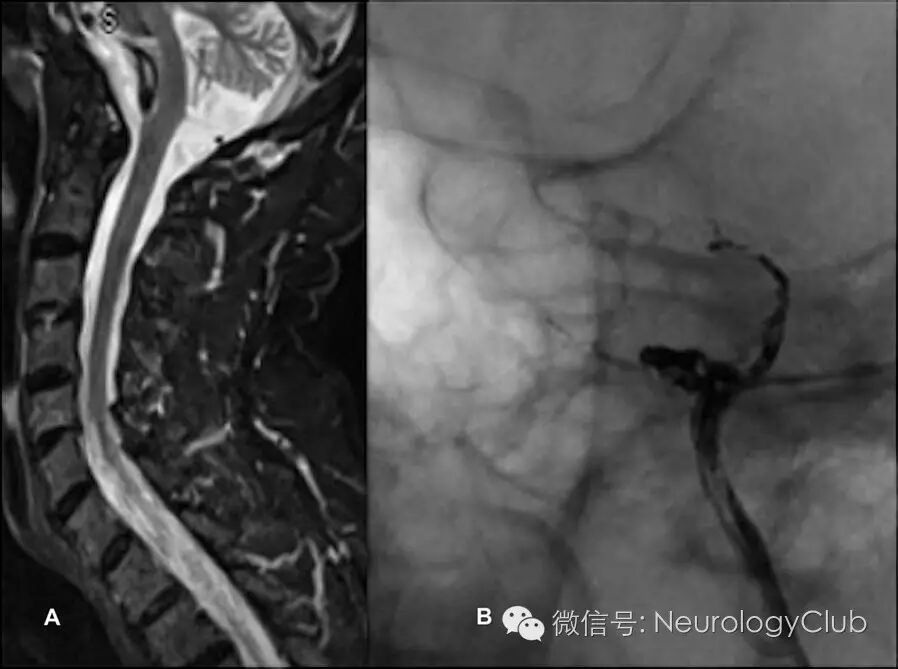

MRI提示弥漫颈髓肿胀以及脊髓前静脉扩张。这些改变提示颅内硬脑膜动静脉瘘(DAVF)伴髓周静脉引流,后经脑血管造影证实。该瘘的供血来自脑膜中动脉和左侧小脑上动脉(图2)。尝试Onyx栓塞脑膜中动脉不幸失败。改用Histoacryl经动脉栓塞左侧小脑动脉获得成功。1年后,患者可脱离工具轻松行走。MRI和脑血管造影可见脊髓水肿和DAVF消失(图3)。

(图3:Histoacryl动脉栓塞治疗后6月复查脊髓MRI矢状位T2WI[A]和脑血管造影[B]可见信号异常好转,硬脑膜动静脉瘘消失)